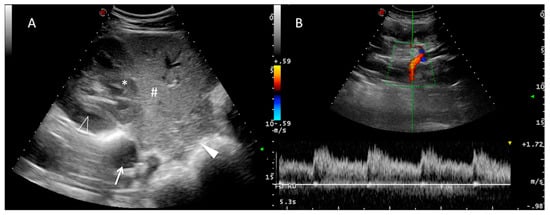

3.1. B-Mode US

3.2. Doppler US